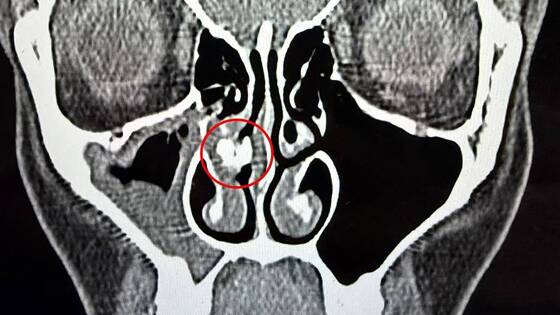

Все изменилось в 2025 году, когда Рейбо обратилась в больницу с синуситом — воспалением слизистой оболочки придаточных пазух носа. Врачи сделали ей компьютерную томографию и обнаружили внутри одной ее ноздри инородное тело неизвестного происхождения.